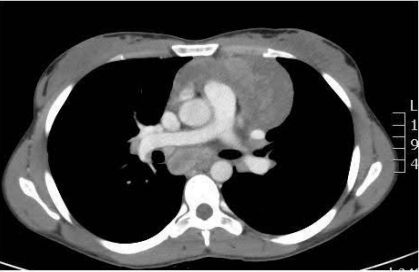

Linfoma ao lado direito do mediastino. Fonte: Acervo de aulas do Grupo MedCof.